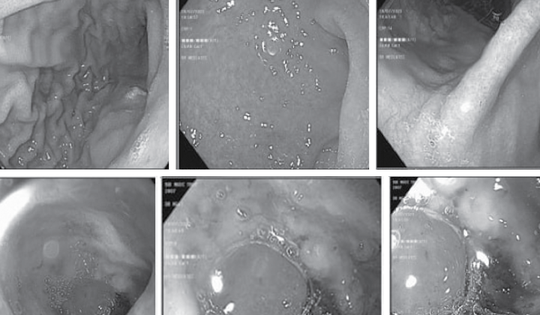

Nhiều trẻ xuất huyết tiêu hóa, bác sĩ khuyến cáo đề phòng biến chứng

Thời gian vừa qua, Bệnh viện Đại học Y Hà Nội tiếp nhận nhiều bệnh nhi xuất huyết tiêu hoá do loét dạ dày tá tràng. Bác sĩ khuyên cáo nếu không được phát hiện sớm có thể dẫn đến nhiều biến chứng nguy hiểm.